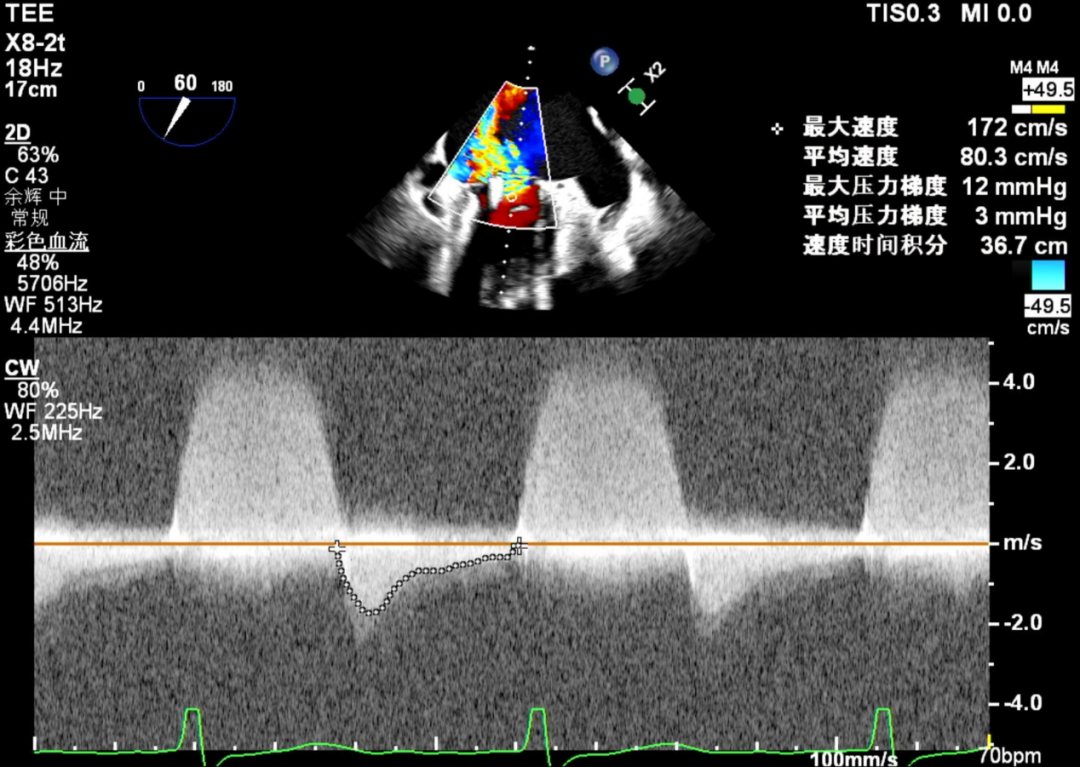

第1枚夹子释放后压差

送入第二枚SW0609(短宽型)二尖瓣夹,使其紧贴第一枚夹子。在食道心脏超声三维多平面重建(3D-MPR)引导下,将夹子跨瓣送入左心室。首次尝试捕捞并夹持瓣叶后关闭夹子,外侧反流量仍较多;随后反转夹子并重新捕捞夹持成功,此时前后叶活动均受限,外侧反流显著减少。释放夹子后,三维超声显示组织桥稳定,反流减轻至轻中度,平均跨瓣压差未见狭窄征象,肺静脉逆流亦有所改善。

将SW0609型号二尖瓣夹(短宽型)送入左心房后,于2区进行轨迹测试与方向调整,使系统整体靠近病变区域,完成左心房定位,夹臂方向调整至12点钟方位。确认轨迹与方向满意后,充分释放系统张力。在3D-MPR引导下,将系统送入左心室,于2偏3区进行捕捞夹持,可见前后叶Bouncing明显。夹子关紧后,3D超声显示夹子方向良好,组织桥稳定,瓣叶活动受限显著,内侧反流明显减少,外侧仍残留中央型反流。平均跨瓣压差提示未造成瓣膜狭窄。为进一步减少反流,计划在外侧追加植入第二枚SW0609(短宽型)二尖瓣夹。